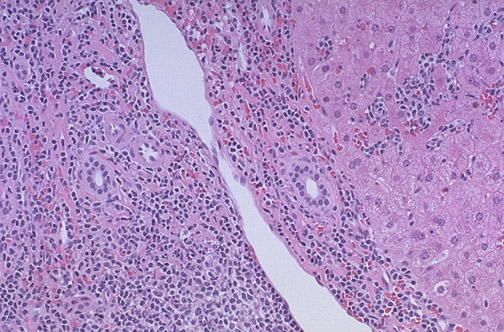

These infiltrates in the liver are composed of small lymphocytes. The involvement of tissues in cases of chronic lymphocytic leukemia (CLL) is known as small lymphocytic lymphoma (SLL). This disease, CLL/SLL, has an indolent course.